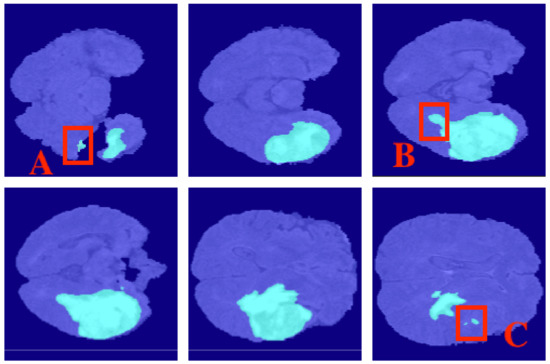

4.2. Segmentation Results

5.6.1. Segmentation Boundary Loss

5.6.2. Third Dimensional Information Loss